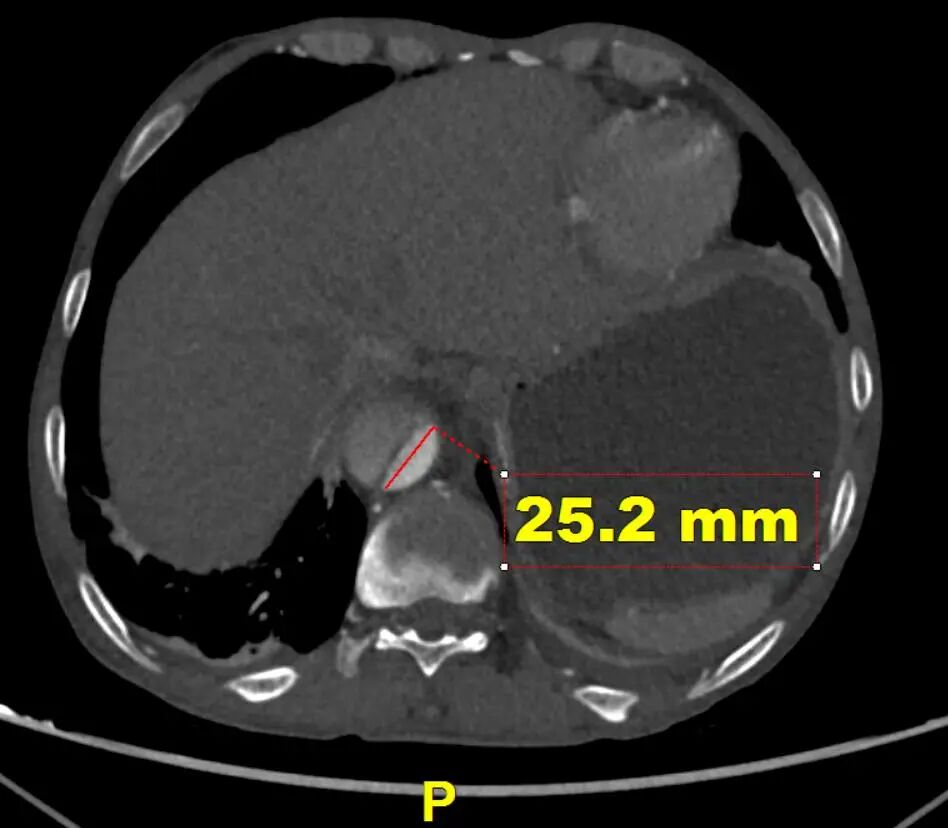

CTA提示患者主动脉弓型为Ⅲ型弓,左侧椎动脉为优势动脉,夹层累及至双侧髂外动脉,腹腔干动脉,肠系膜上动脉及左肾动脉为真腔供血,右肾动脉为真假腔供血,左侧胸腔少量积液。

远端真腔长轴直径

LSA后缘主动脉直径

对于此病例,近端未见明显破口,计划从左锁骨下动脉后缘锚定保证椎动脉血供,远端覆盖降主段主要破口,支架远端尽量处在相对直段的血管降低损伤血管风险。结合近端血管直径及远端真腔长轴直径计划近端:CADS支架 TGMR313120+远端CTAG TGU262610。